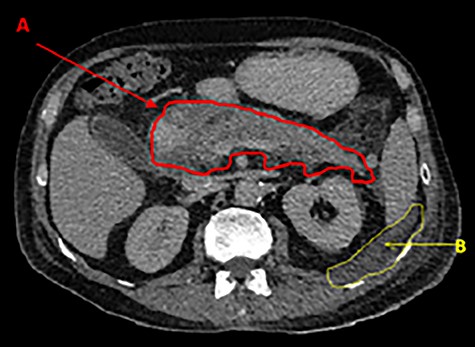

Contrast CT showing inflamed, enhancing pancreas (A) and the presence of paranephric fluid in the retroperitoneal region (B).

palpation of the epigastric region. No other systemic findings were noted at this time. Serum amylase was raised (727 U/L, normal range 30–110 U/L) [3]. Ultrasound of the abdomen revealed sludge within a thin-walled gallbladder and a diagnosis of acute pancreatitis secondary to gallstones was made. The patient’s severity stratification according to the Glasgow Criteria was 1, scoring only for age over 55 years [4].

Four days after admission, the patient complained of pain in his left lower abdominal quadrant. A tender, irreducible, erythematous swelling was apparent in the patient’s left groin. CT scans (Fig. 1) revealed extensive peripancreatic fluid with some infiltration of the left paracolic gutter, as well as extensive subcutaneous oedema and a small left inguinal hernia that did not contain any bowel loops (Fig. 2). The hernia became more painful and repeat CT scans showed a marked increase in the volume of fluid surrounding the pancreas and the degree of fluid tracking to the anterior and posterior paranephric spaces and left paracolic gutter was also greater than before.